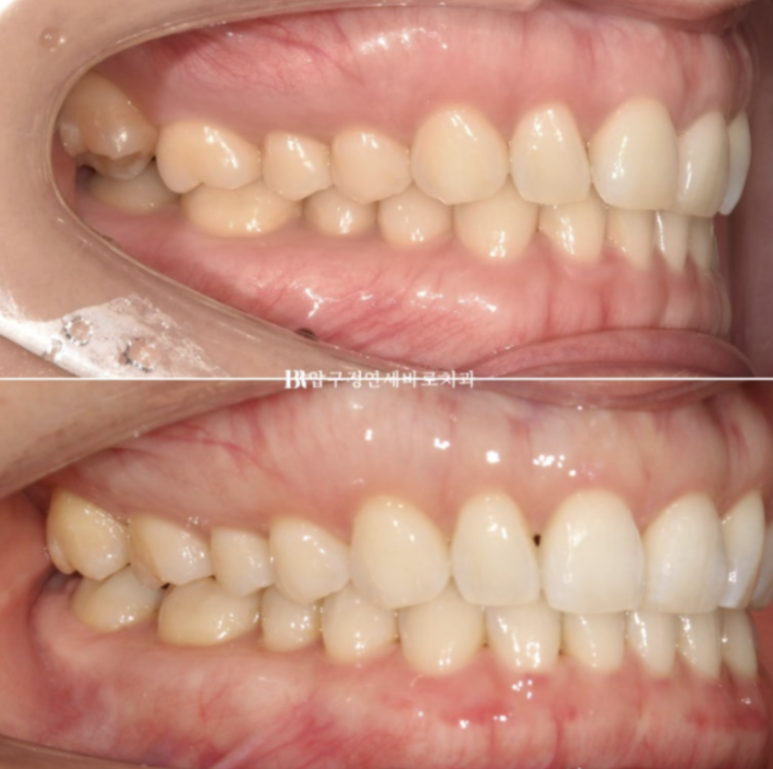

중심선 불일치 그리고 오른쪽의 맨 뒤 큰어금니 바깥으로 나가 있는 가위교합이 정면에서도 잘 보입니다.

23.07

오른쪽 맨 뒤 큰 어금니의 가위교합이 보이고 왼쪽은 송곳니와 앞니 벌어진 공간이 보입니다.

인비절라인 라이트로 이 모든 것을 해결하고 치료에 들어갑니다.

24.5

Q 인비절라인으로 교합이 제대로 맞지 않는다는 말이 사실인가요?

A. 이는 일부 오해입니다. 정확한 진단과 치료 계획, 그리고 필요 시 보조 장치 활용이 이루어진다면 인비절라인으로도 기능적으로 안정적인 교합을 충분히 만들 수 있습니다. 본 사례처럼 어금니 교합까지 안정적으로 마무리되는 결과도 많습니다.

가위교합이였던 우측 상악 제 2대구치 교합도 잘 유지가 되고 있습니다.